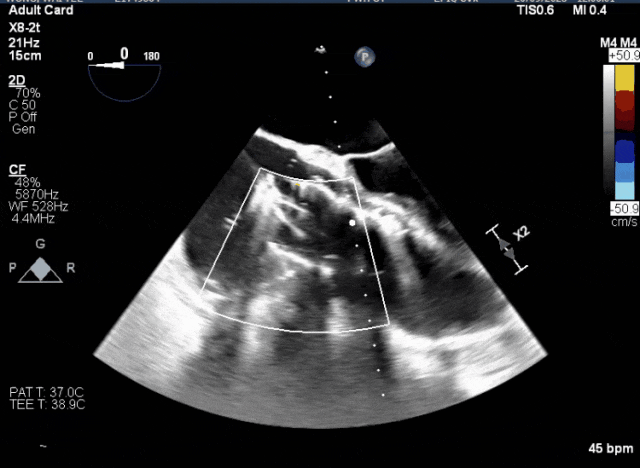

術(shù)中TEE成像困難,偽影干擾

術(shù)后DSA、超聲顯示人工瓣膜穩(wěn)定性良好,瓣葉啟閉正常,無瓣周漏